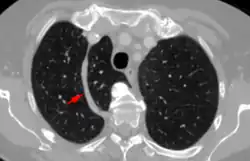

De lobus venae azygos als anatomische variant van een normale long wordt meestal als toevalsbevinding ontdekt bij radiologisch onderzoek. Op longfoto's is de fissura venae azygos namelijk als een gebogen witte lijn zichtbaar in het mediale bovenveld van de rechterlong.[1]